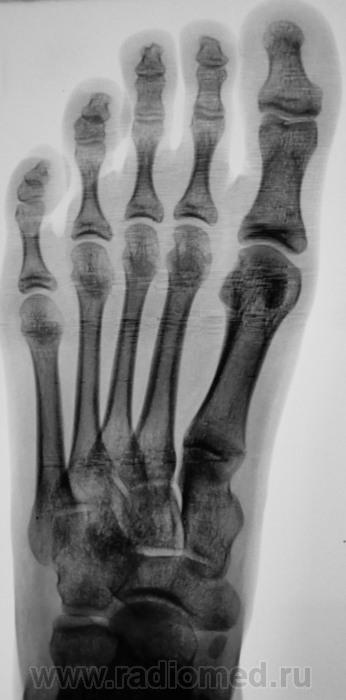

Ровненько и кругленько.Не отломок.

Отломки так не выглядят.

Os tibiale externum. Покажите хирургу анатомический атлас

Да, Королюка.

Или в инете загуглит ))) http://radiopaedia.org/articles/os-tibiale-externum... или http://nl.wikipedia.org/wiki/Os_tibiale_externum

Хирург у нас с большими "понтами", свою точку зрения имеет.

Но сейчас с "точкой зрения" стало туговато. Протокол рентгенолога стал обязательным.

Вывести косточку в оптимальную проекцию, затем анатомия совместно с хирургом.